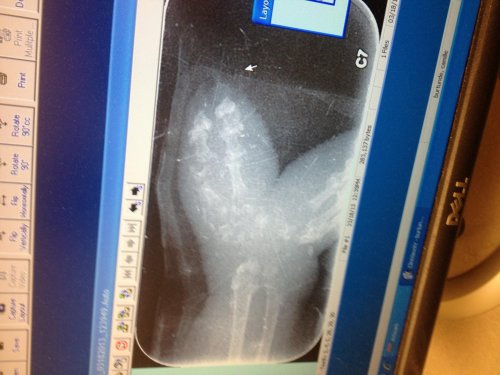

I agree this is a case of severe osteomyelitis and yes amputation is the best therapy if survival is the main objective. The longer we leave the infected bone the increased likely hood for sepsis, etc.

Chameleons do fine with amputation which will allow a faster resolution and less long term stress.

Continue aggressive antibiotics for 3-4 weeks post op.

This is a common problem in chameleons and is not usually related to calcium issues.